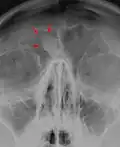

Osteoma of the frontal sinus seen on x-ray

Osteoma of the frontal sinus seen on x-ray -